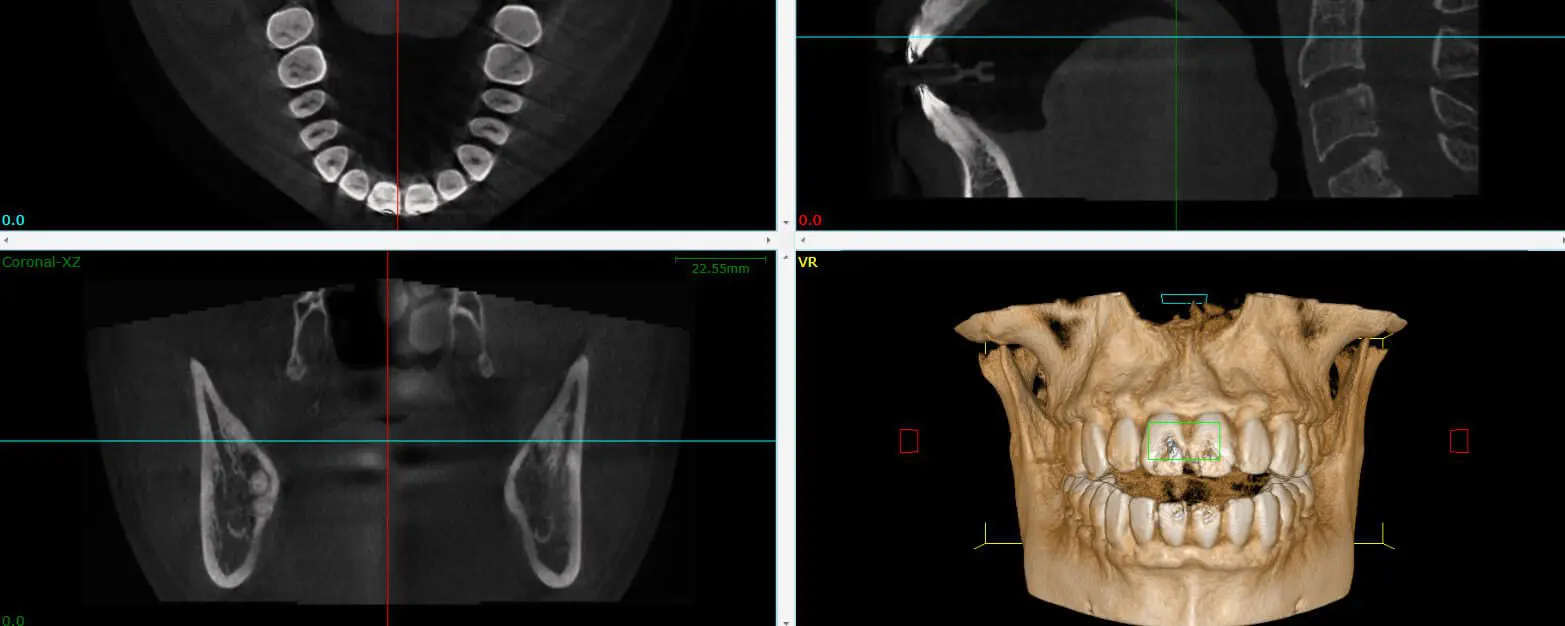

3d cone ct scan

• Cone Beam 3D Imaging